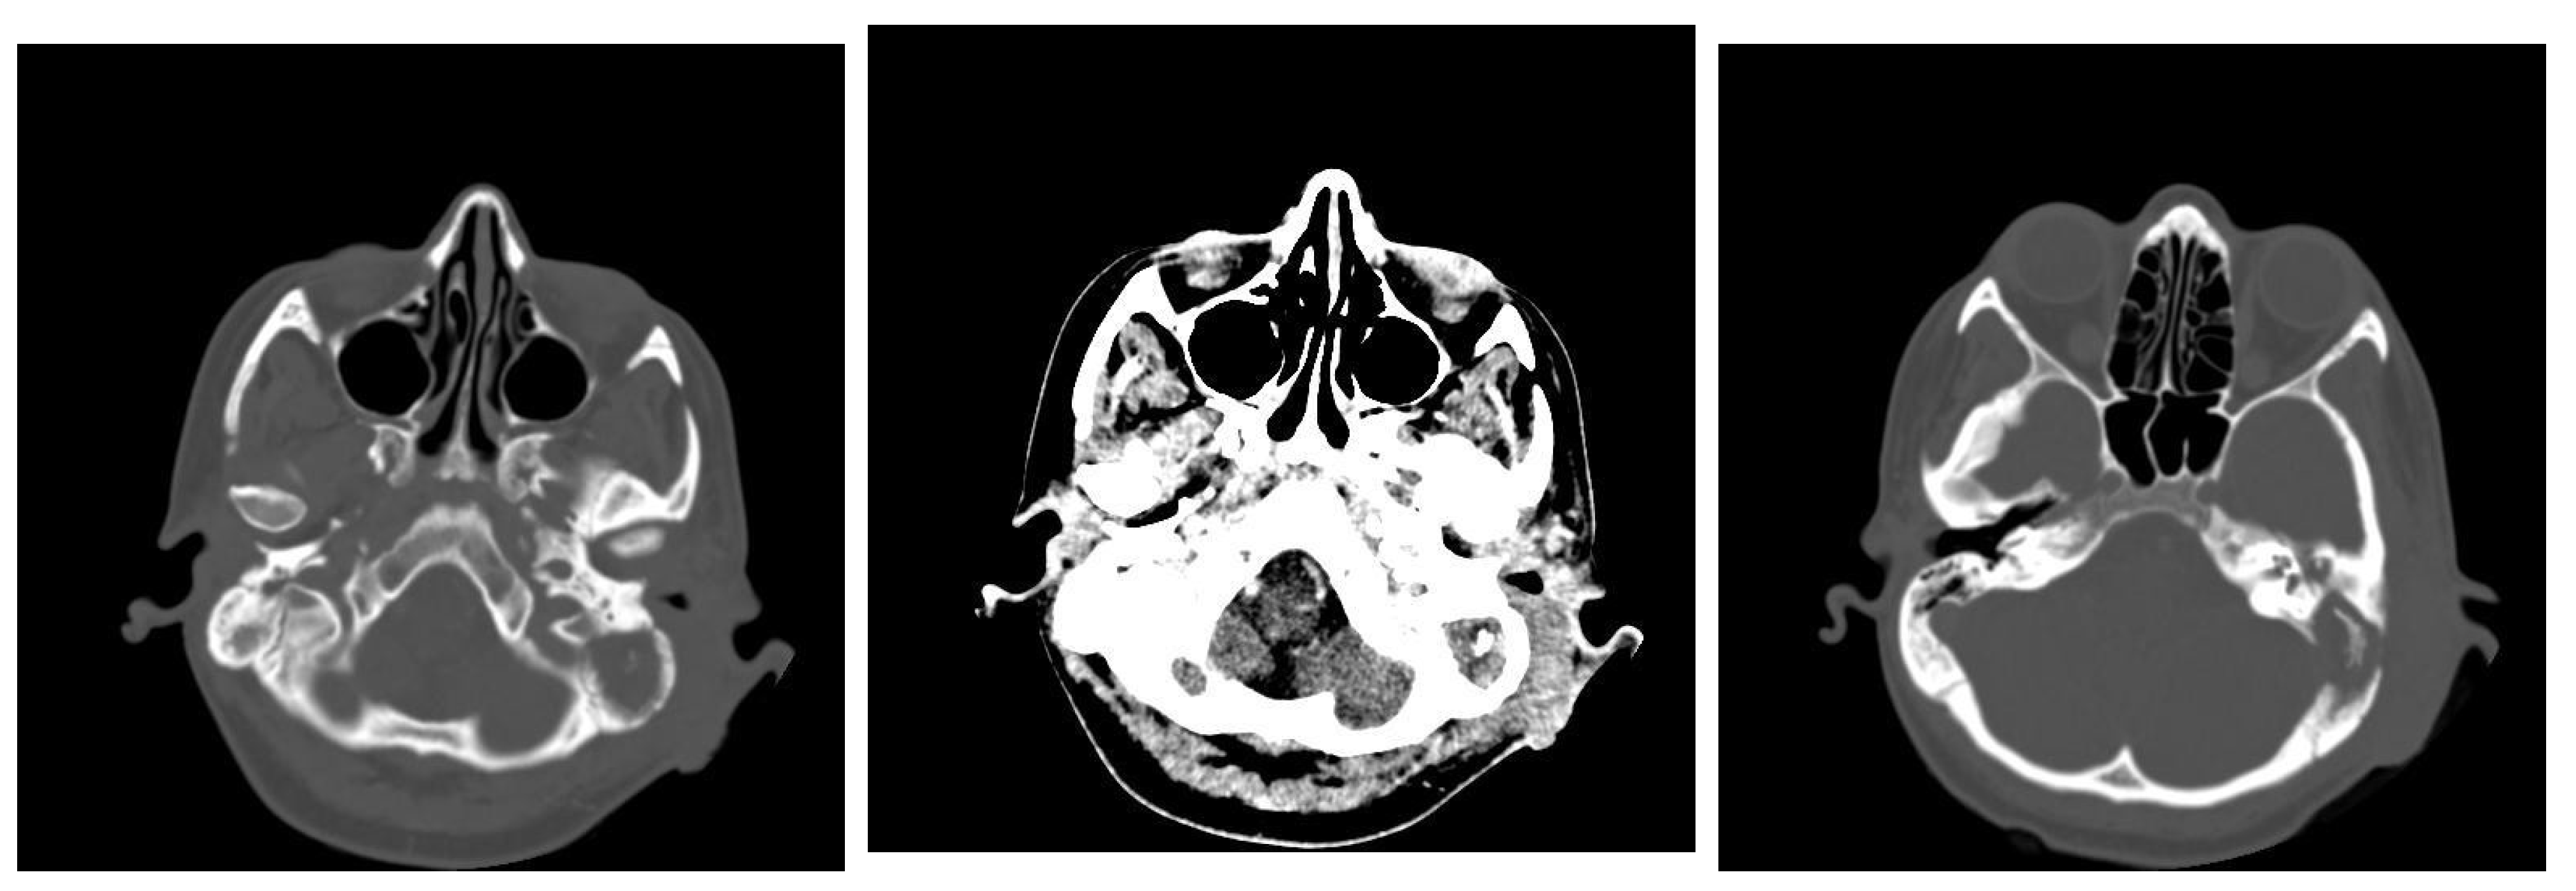

3.1.2. Computed Tomography and Magnetic Resonance Imaging

| CT Aspects | Number of Patients | Percentage |

|---|---|---|

| Fluid accumulation | 168 | 100% |

| Osteolysis | 152 | 90.47% |

| Osteocondensations | 128 | 76.19% |

| Cholesteatoma | 48 | 28.57% |

| Exocranial extensions | 48 | 28.57% |

| Intracranial extensions | 24 | 14.28% |

| Changes to the external auditory canal | 68 | 40.47% |

| Ossicular chain damage | 144 | 85.71% |

| MRI Aspects | Number of Patients | Percentage |

| Edema | 128 | 100% |

| Cholesteatoma | 40 | 31.25% |

| Exocranial extensions | 40 | 31.25% |

| Intracranial extensions | 32 | 25% |

| Inner ear damage | 20 | 15.62% |